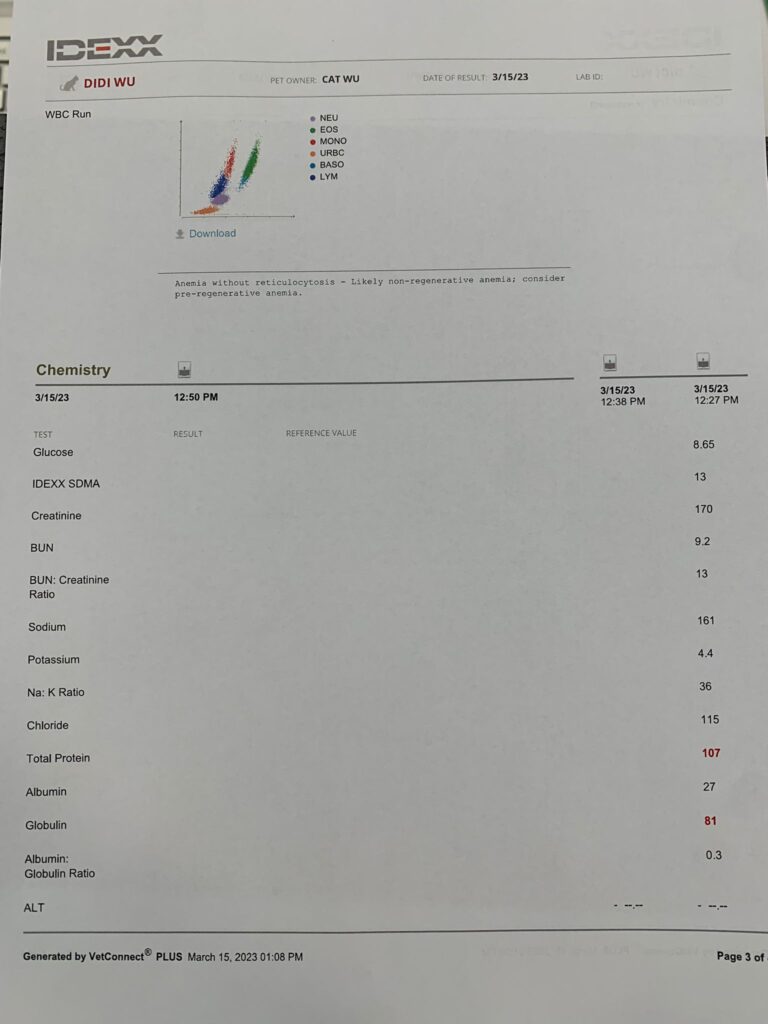

Hct kidneys liver lytes all ok. Only glob and glu higher most prob due to stress/ mouth. Nothing else I can do. Exactly why I know didi is under the category of no need to see vet cos nothing significant can be found n done. Have to whack more money on bupre. dr told me to try im for better absorption. He tried open his mouth – fail badly. Too pain.

HCT 29.5%, dr nally say she don’t like her EOS 3.24, but it’s a gone down figure cos March he had fenbendazole alr. Will tell them deworm him today. Alt 177 – continue ornipural. GGT 6, restart ursofalk 65mg. 15mg/kg in short. add on Clav 14 days, 0.22ml and anti histamine jabs (expire dec 23) – price $188 don’t make sense so didn’t buy.

HCT 29.2% – monitor le. Alt 216. Think ornipural working ok for him – continue, dr Brandon says that’s what he use last time like a supplement so no harm giving.

alt can read now, not good but can read 25x – will continue w Sam e.

Still can feel the enlarge spleen and liver enlarge too – so retake Chem 10

Cos dr d needs alt glob

HCT 29.2%, Erm drop leh. (Semintra loh) – but have to continue (UPC 0.43) and Clav have to continue

Sdma 13 back to normal

Alt can’t read for 2 times – his liver Erm must check again.

Noon: dr d “Polyclonal for didi, so no clear tumor suspect. This happens in chronic inflammation, either viral bacterial or parasitic. Or immune mediated. but very unlikely the tumor we thought…. myeloma would not look like this. so can almost 95% rule out. or try investigate lot further, maybe try to get sample from the enlarged liver or lymf nodes. lot more invasive. have you given him an antibiotic trial at some point already? dewormer?” – reminded dr d that didi alr on Clav jab 0.19ml

Sdma 19

Glob wbc producing tumor – send out to see the diff type of glob results. If one type of glob go up, then highly is tumor. If all go up then not as bad.

Sg 1.014 – Dilute urine, losing a little protein in urine, can try low dose semintra 1mg/kg (nowadays vet give 2mg per kg, n they finally acknowledge that 10-15% become anemic as a side effect)

I trying 0.5mg/ kg and review to make sure rbc stable n upc go down. UPC 0.39

Rbc down to 6.12, lucky HCT still 30.3%.

Wbc NEU all go up.

45mg once daily ursofalk for the gall bladder too.